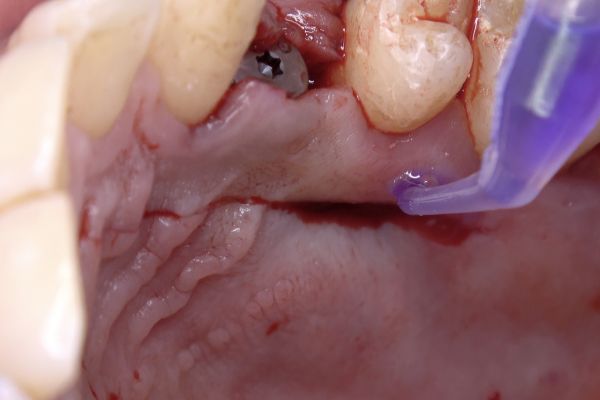

Manejo quirúrgico y restaurador de un implante en área estética y evaluación volumétrica tras un injerto de tejido conectivo desepitelizado. Descripción de un caso clínico

El reto del abordaje quirúrgico en la rehabilitación sobre un implante unitario en un caso de alto requerimiento estético del sector anterior. Descripción a propósito de un caso

The challenge of the surgical approach in the rehabilitation of an anterior sector unitary implant in a case of high aesthetic requirements; case report